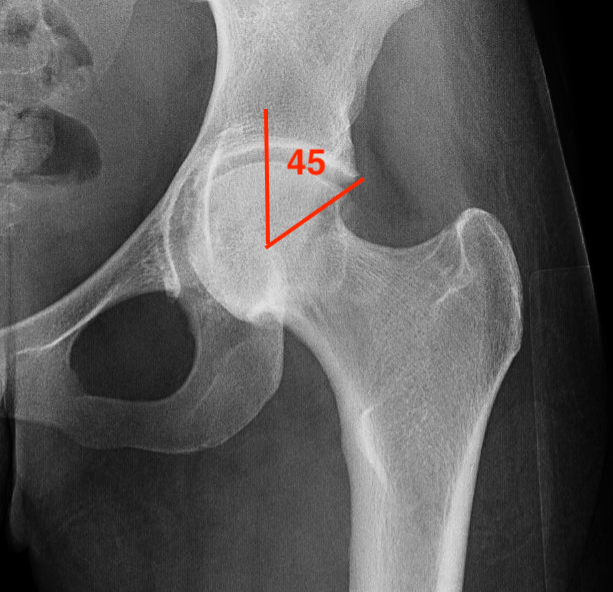

45 and 90 degree Dunn view

Look for Cam morphology

Small Cam on Dunn view Large anterior Cam on Dunn view

Alpha angle

Measurement

- centered in the center of the femoral head (best fit circle)

- formed by two lines

- one line center of the femoral neck axis

- a line where the femoral head leaves a best-fit circle

- higher alpha angle with Cam lesion

Alpha < 55 degrees Alpha > 55 degrees